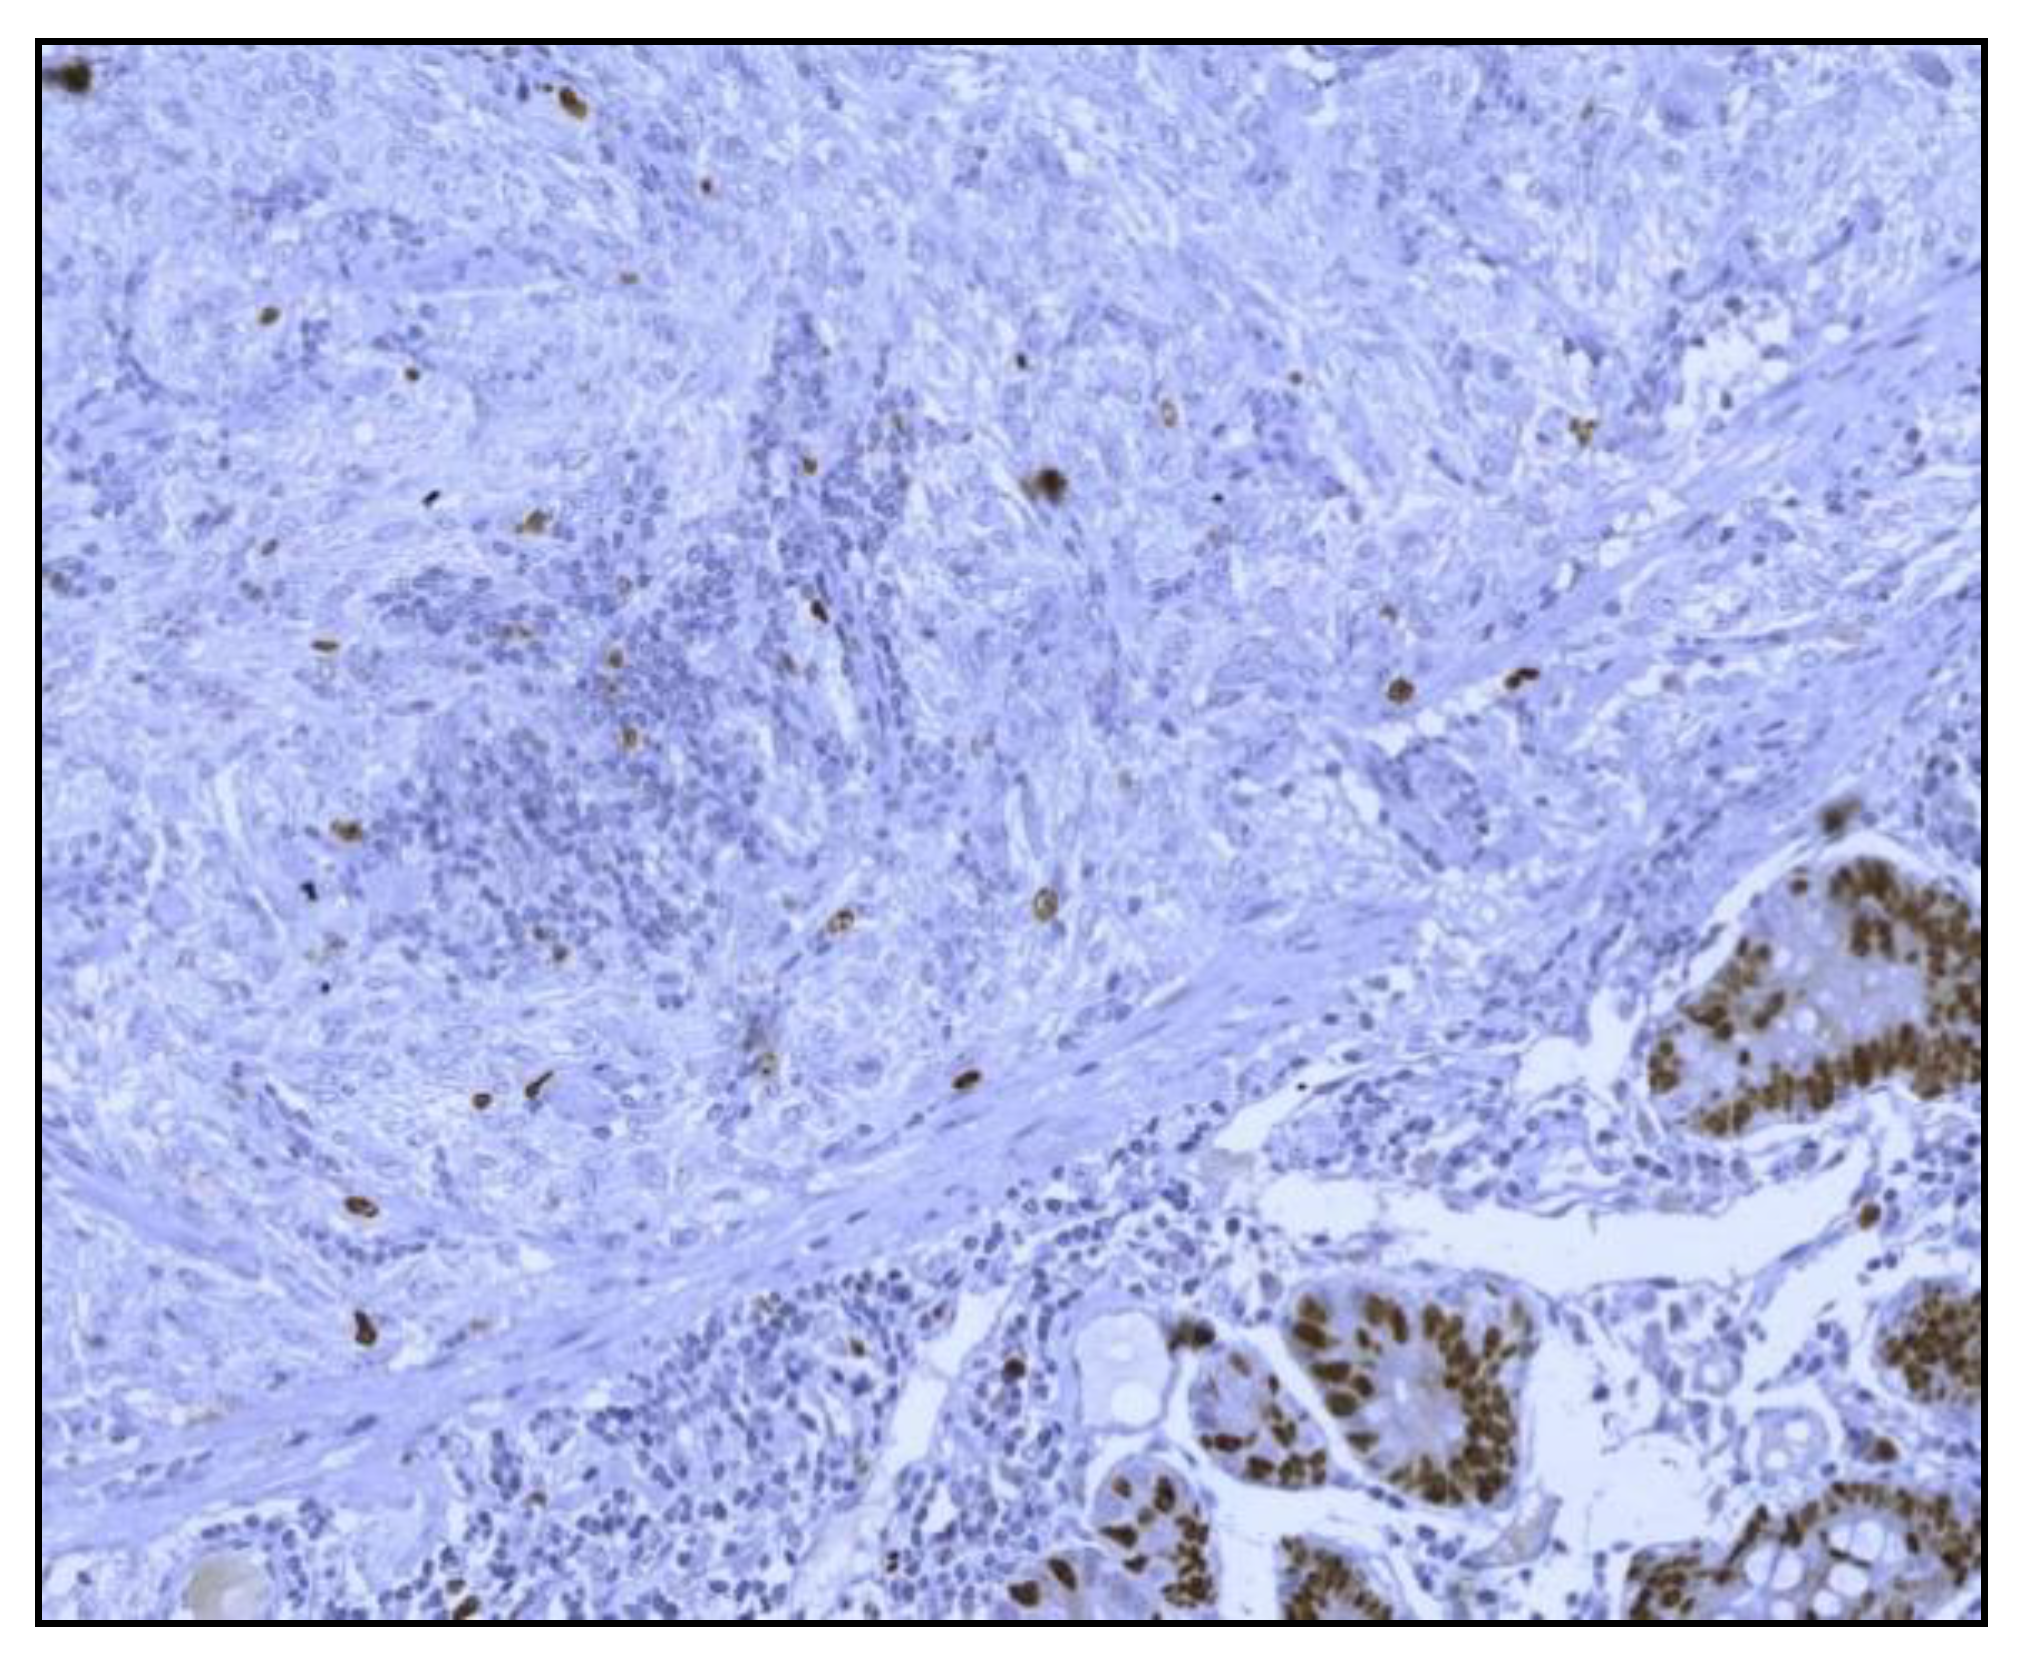

The histological examination of the specimen demonstrated an intramural small tumor −2 cm in diameter with intraluminal growth and obstruction. The final diagnosis was a high-grade ulcerated GIST with classic spindle cells, clear resection margins and no lymph node invasion (Figure 4). Mitotic activity was 12/50 on HPF (High-Power Fields). Ki67 proliferation marker labels 10% of the nuclei (Figure 5).

Figure 5.

Microscopic finding exhibiting a positive immunohistochemistry for Ki 67 (Ki67 staining; 40x optical magnification.